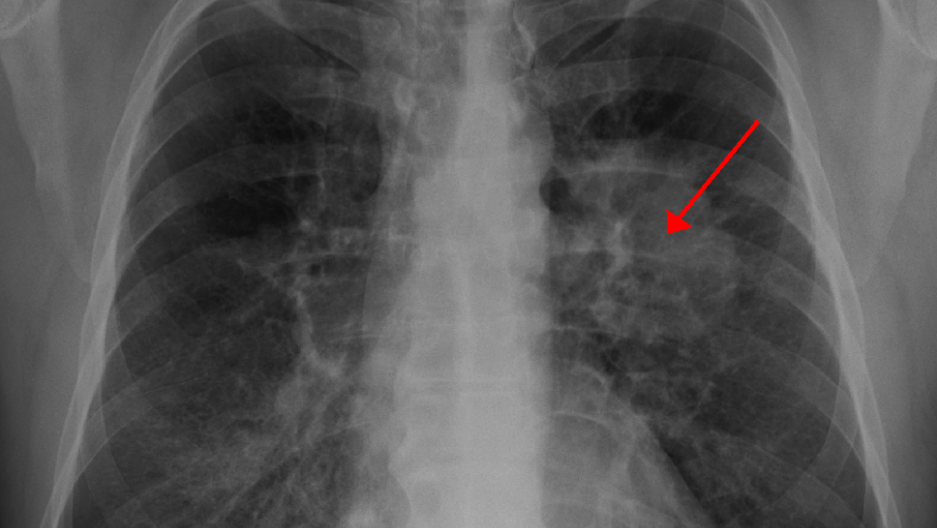

Ảnh minh họa